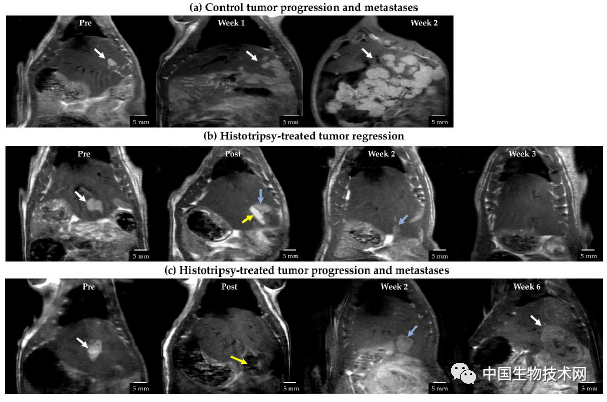

在這項新研究中,研究人員在原位、免疫活性、轉移性齧齒動物肝細胞癌模型中,評估了超聲組織切除術的治療效果。

在實驗中,22只肝細胞癌大鼠模型被分為兩組,一半作為對照組不接受任何治療;另外一半使用超聲組織切除術治療,目標是消除腫瘤體積的50%到75%。

治療後,研究人員檢測腫瘤進展、轉移和免疫標誌物的跡象,以確定治療的成功程度。

他們發現,對照組大鼠的預後非常糟糕,所有11只的腫瘤都有繼續進展和轉移的跡象。三週後,腫瘤已達到倫理協議允許的最大尺寸,動物被實施了安樂死。

而經過超聲治療的大鼠要好得多,它們不僅在治療過程中沒有出現併發症或副作用,而且大多數(11只中的9只)顯示出腫瘤消退,並且在研究的剩餘時間(大約10周)中經歷了無瘤生存期**。**但由於新冠疫情導致實驗室關閉,治療組的大鼠也被執行了安樂死。

研究人員發現,即使是部分治療也使81%接受治療的大鼠腫瘤完全消退。相比之下,100%的對照組大鼠顯示出腫瘤繼續發展。